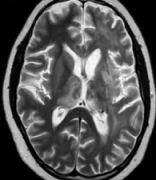

星形细胞瘤是始于星形脑细胞的肿瘤,称为星形细胞。星形胶质细胞是一种胶质细胞。神经胶质细胞将神经细胞固定在适当的位置,为它们提供食物和氧气...

脑部胶质瘤是怎么形成的?脑部正常的胶质细胞可产生三种类型的肿瘤。星形胶质细胞将产生星形细胞瘤,少突胶质细胞将产生少突胶质细胞瘤,室管膜瘤...

胶质瘤的症状表现,在临床上,胶质瘤患者表现出的症状与肿瘤部位、肿瘤大小有较大关系。脑胶质瘤患者一般会出现恶心、呕吐、视乳头水肿等症状;额...

不同类型的胶质瘤有不同的好发部位。例如,星形细胞瘤多见于大脑半球,儿童多见于小脑;几乎全部的胶质母细胞瘤都发生在大脑半球;髓母细胞瘤发生...

神经胶质瘤又称胶质瘤,包括星形细胞瘤、少突胶质细胞瘤、混合性神经胶质瘤、室间隔膜瘤,根据它们增长的速度或快慢,每种类型都可以分为I级到IV级...